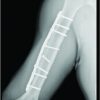

A 72-year-old male with a past medical history of a right knee medial meniscal tear and chondromalacia, type 2 diabetes mellitus, coronary artery disease status post placement of two right coronary artery stents, hypertension, and hyperlipidemia presented to his PCP for evaluation of persistent acute left knee pain. He reported that 5 weeks prior he had slipped getting out of his hot tub. He described a sudden split motion with extreme hyperextension of the left hip with hyperflexion of the right hip. After, he experienced sudden bilateral knee pain predominantly in the left knee with no associated edema or bruising. The pain in the right knee resolved without treatment. His chief complaint was an inability to extend his knee or lift his leg, which unfortunately caused him to fall 4 days before the visit. Otherwise, he was in his normal state of health. On examination, he was noted to have tenderness to the proximal medial collateral ligament, iliotibial band, patella tendon, and quadricep tendon. There was no swelling or deformity and he demonstrated full range of motion. Motor testing demonstrated 1/5 strength to left knee extension and hip flexion. A quadriceps rupture was suspected. Referrals were placed for a left knee magnetic resonance imaging (MRI) and a consultation with the orthopedic department for further evaluation. The patient was then seen in the orthopedic clinic the following week. He reported continued left knee pain and weakness. The examination revealed no ligamentous injury. There was no defect to the quadricep tendon but there was noticeable quadricep atrophy. A neurologic examination showed numbness to the medial aspect of the knee, and he demonstrated an inability to fire the quadriceps. He also described burning pain radiating down the front of his leg. Radiographs of the left knee showed no acute process, specifically no patella baja or alta. MRI of the knee showed no evidence of a quadricep rupture. The MRI did show chronic degenerative changes in the knee. After imaging review and evaluation, femoral nerve palsy was suspected. The patient was sent for an electromyography (EMG) and an MRI of the femur to assess the femoral nerve’s continuity. He was also referred to physical therapy for quadriceps strengthening. Gabapentin therapy was started to help with continued pain. The EMG and femur MRI were completed the following day. The EMG showed an active and severe left L3 lumbar radiculopathy. The MRI showed no signs of injury to the left thigh nerves. After these findings were reviewed an MRI of the lumbar spine was placed. The MRI of the lumbar spine was completed the following week. This showed multilevel degenerative changes, spinal canal narrowing, and bilateral neuroforaminal narrowing at L4-L5. This prompted an order for a lumbar plexus MRI to be completed the next day. This demonstrated injury to the pelvic portion of the femoral nerve with mild enlargement and higher-than-normal signal intensity. MRI Fig. 1 and 2 show L3/L4 fascicular enlargement consistent with femoral nerve injury.